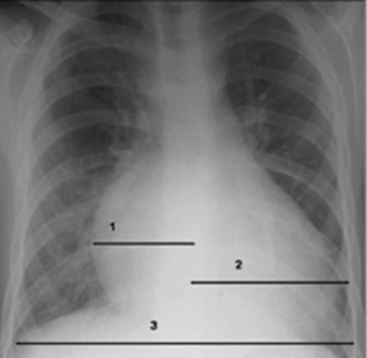

The size of the heart is quantified on AP or PA view by calculation of a ratio of the width of the heart to the width of the thorax, called the cardiothoracic ratio. To obtain the cardiothoracic ratio, the heart is measured between vertical lines drawn at its widest margins (from the center) on the right and left, and the chest is measured at the costophrenic angles on the inside of the rib cage (Fig. 10-11).

image

Fig. 10-11 Cardiothoracic ratio measurement. This chest film demonstrates the proper measurement of the cardiac silhouette on the right (from midline to widest point; line 1) and left side (from midline to widest point; line 2) and the inner diameter of the chest (line 3). The added width of the right and left side widest measurement divided by the widest point of the inner diameter of the chest is used to calculate the cardiothoracic ratio.

Beyond the newborn period, the heart’s width does not normally exceed half the width of the thorax. The cardiothoracic ratio in newborns is normally up to 0.55. In older infants and children up to 6   years of age, a ratio of 0.45 is normal. Between 6 and 12   years of age, a cardiothoracic ratio of up to 0.44 is normal.21 A convenient rule is that the cardiothoracic ratio in children is normally 0.5, plus or minus 5% to 6%, and it is typically larger in neonates and smaller in older children. An increase in the cardiothoracic ratio suggests the possibility of cardiomegaly. However, a poor inspiratory film and AP (compared with PA) chest radiographs will affect the accuracy of the cardiothoracic ratio.7,16,17 For practice, calculate the cardiothoracic ratio in Fig. 10-2, A. The ratio is 0.52.